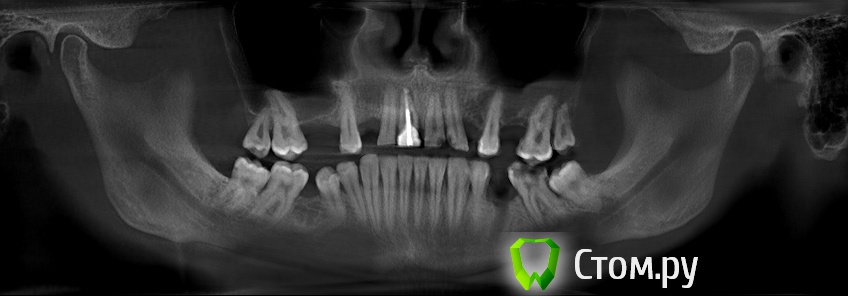

sergey765 Опубликовано 11 июня, 2014 Автор Поделиться Опубликовано 11 июня, 2014 посмотрите пожалуйста КТ. Ссылка на комментарий

sergey765 Опубликовано 11 июня, 2014 Автор Поделиться Опубликовано 11 июня, 2014 могу вам ещё снимков выложить.их довига. беспокаят меня боли после удаления .прошло 5 недель. снимки девушка лет 20 эти смотрела. сказала что у меня там инфекции дофига. типа давай я тебя на понедельник к хирургу запишу. он ранку вскроет. прочистит Ссылка на комментарий

Bier Опубликовано 11 июня, 2014 Поделиться Опубликовано 11 июня, 2014 это все не информативные кадры, в прикрепленных темах есть инструкция, выкладывайте КТ целиком, наш рентгенолог скачает и выложит срезы. 3 Ссылка на комментарий